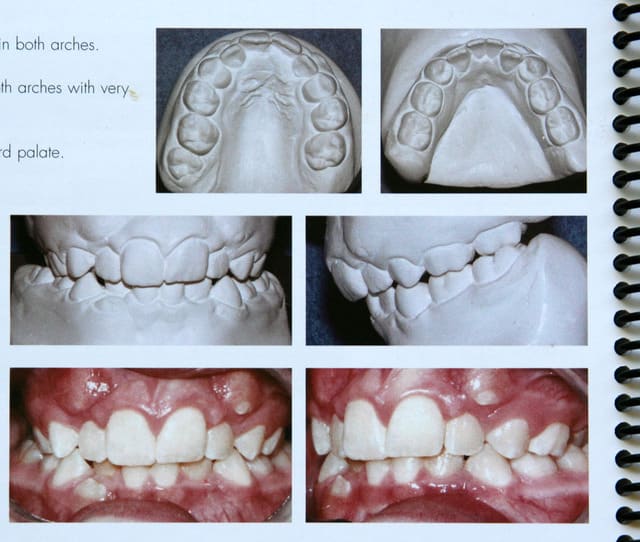

bjc

19/02/2007 à 10h37

chers confrères orthoconscients

si je vous ai montré ce cas de D.D.M. c’est afin de vous prouver que les extractions sont de moins en moins nécessaires.

Si j’arrive à le faire, en n’étant ni prof, ni membre de sociétés réputées, c’est qu’avec les techniques actuelles, ce n’est pas très difficile

C’est à la portée de tout orthodontiste

@+ Bjc.